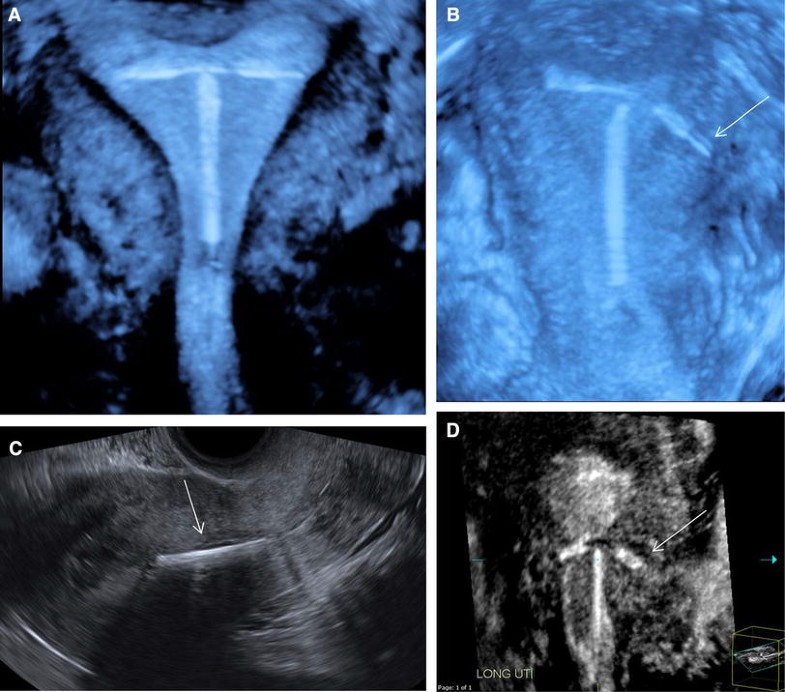

From sononotes.com

Accurate detection of IUD placement using 3D ultrasound Sononotes Thickened Endometrium With Iud endometrial hyperplasia is a condition in which the lining of your womb becomes too thick. the current results suggested that mirena iud could inhibit the growth of the thickness of endometrium compared. this fact sheet is for women who have been told that the lining of their uterus (endometrium) has become thicker and. when the endometrium,. Thickened Endometrium With Iud.